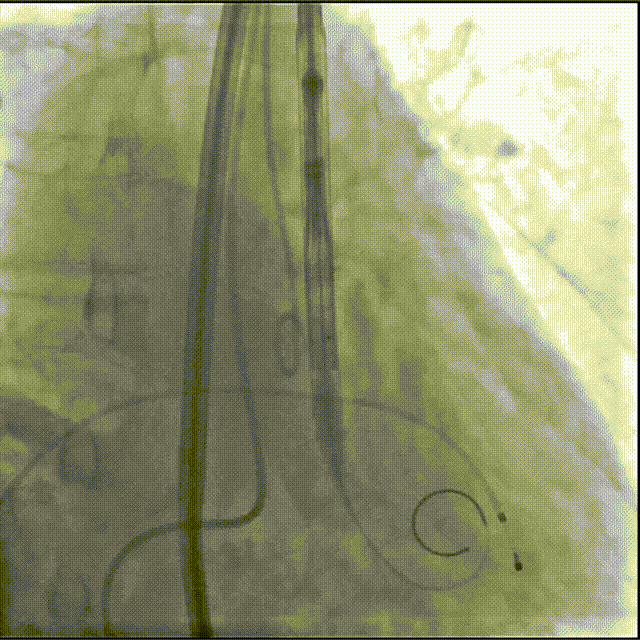

初始造影确定瓣环位置

20mm球囊预扩,无腰有漏;选择27号瓣膜可充分封堵

瓣膜0位定位释放,导丝保持张力,保证同轴性

瓣膜展开后造影评估瓣膜位于0位,无瓣周漏

多角度评估,瓣膜位置可,同轴性佳,可以脱钩释放

脱钩后造影,瓣膜无位移,无瓣周漏